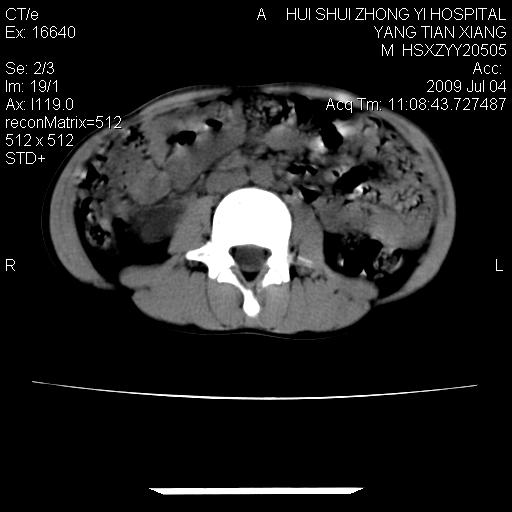

肝右叶胆管内见条状高密度影,脾脏增大,双肾上腺无异常;右肾正常结构消失,其实质内见类圆形低密度灶,ct值范围0-6hu,界清,右输尿管全程伴行多发低密度灶,界清,膀胱壁增厚,腹盆腔未见确切肿大淋巴结。

考虑:1、肝内多发胆管结石并肝内胆管扩张。2、右肾、输尿管多发脂肪瘤,多发平滑肌瘤?建议ct增强检查。4、膀胱壁增厚。

右侧巨输尿管可能。

膀胱壁增厚。

2、右侧巨输尿管并右肾积水可能性大。

右侧巨输尿管并神谕积水,左肾代偿性肥大,脾大,肝内胆管多发结石并胆管扩张。